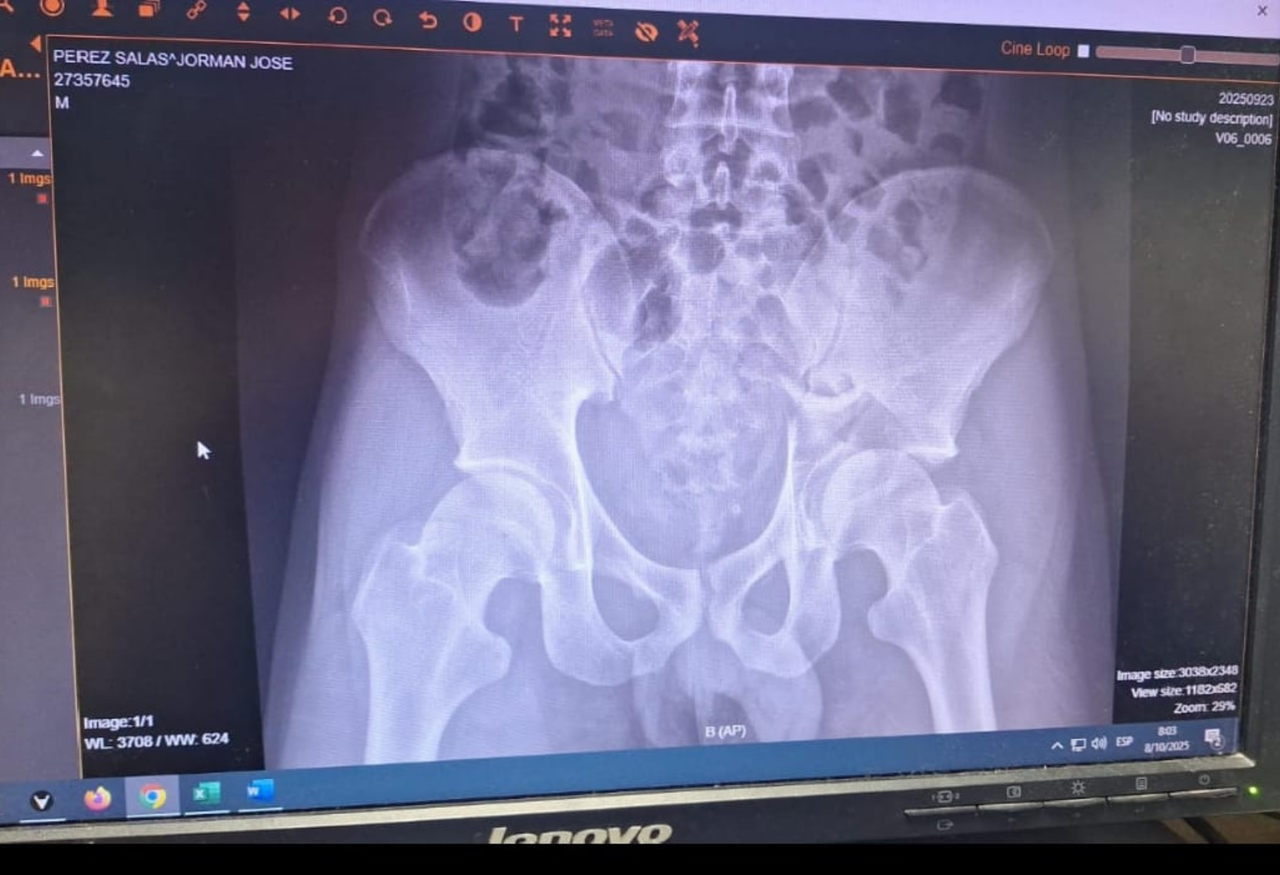

Fractura lateral de cadera izquierda

Ruptura del hueso en la parte externa de la cadera izquierda, generalmente causada por caídas o traumatismos, que provoca dolor y dificultad para caminar.